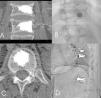

En estos pacientes se realiza un estudio mediante resonancia magnética (RM), empleando secuencias sagitales potenciadas en T1 y secuencias T2 con supresión grasa (STIR).

En las secuencias potenciadas en T1, la fractura vertebral reciente se manifiesta con una disminución de la señal de resonancia. En las secuencias potenciadas en T2 con supresión grasa o STIR, la manifestación es una hiperseñal, fácilmente identificable por la supresión grasa; estos cambios de señal traducen la presencia de edema y se correlacionan con un proceso agudo, susceptible de ser tratado mediante vertebroplastia (fig. 1).

Figura 1. A: resonancia magnética sagital de columna con secuencia espín eco potenciada en T1: las fracturas agudas en L3, L2, T12 que presentan disminución de la intensidad de señal, fracturas vertebrales consolidadas, sin edema, en territorio dorsal medio. B: resonancia magnética sagital con secuencia espín eco potenciada en T2 con supresión grasa, hiperseñal en las vértebras con fractura reciente.